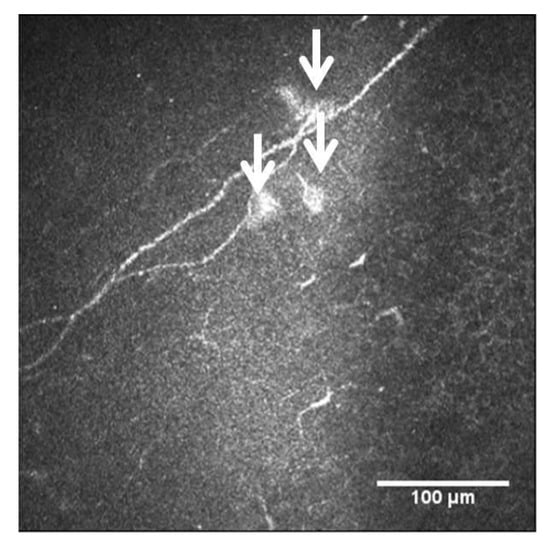

Corneal nerves are suitable for SARS-CoV-2 infection due to their neuroreceptors. Severe COVID-19 infection is associated with systemic neuropathic symptoms and generalized sensory dysfunction in patients with diabetes, including loss of sensation, altered tissue homeostasis and the generation of epithelial ulcers [73,74]. Neuropathological studies have shown SARS-CoV-2 in the cerebrum, cerebellum, cranial nerves, olfactory bulb and olfactory epithelium, with associated microglial activation and lymphoid inflammation. After plasma exchange, an improvement in neuropathy has been observed [75,76,77]. The cornea, as one of the most innervated tissues in human body [78], receives heterogeneous sensory nerves from the ophthalmic branch of the trigeminal nerve. In addition to these sensory fibers, the cornea also receives some autonomic sympathetic nervous fibers, which originate in the cell bodies of the upper cervical ganglion [79,80,81], and some autonomous parasympathetic nervous fibers (from the ciliary ganglion). IVCM is a useful tool to examine the integrity of the peripheral nervous system, even in neurodegenerative diseases [82]. In patients after SARS-CoV-2 infection, microneuromas have been identified in the sub-basal nerve plexus and stromal nerves. In fact, the microneuromas could be the consequence of nerve damage, and thus a sign of nerve regeneration. Additionally, some neuromas have been seen using IVCM as hyperreflective bulbs at the end of the nerves in these patients (Figure 9) [83]. There are some studies that showed fewer corneal nerve fibers and an increase in DCs in patients with active COVID-19 [84] and in long COVID-19 patients, 3–4 months after the infection [85].

Figure 9.

Neuromas in long COVID-19 patient seen with IVCM, white arrows.